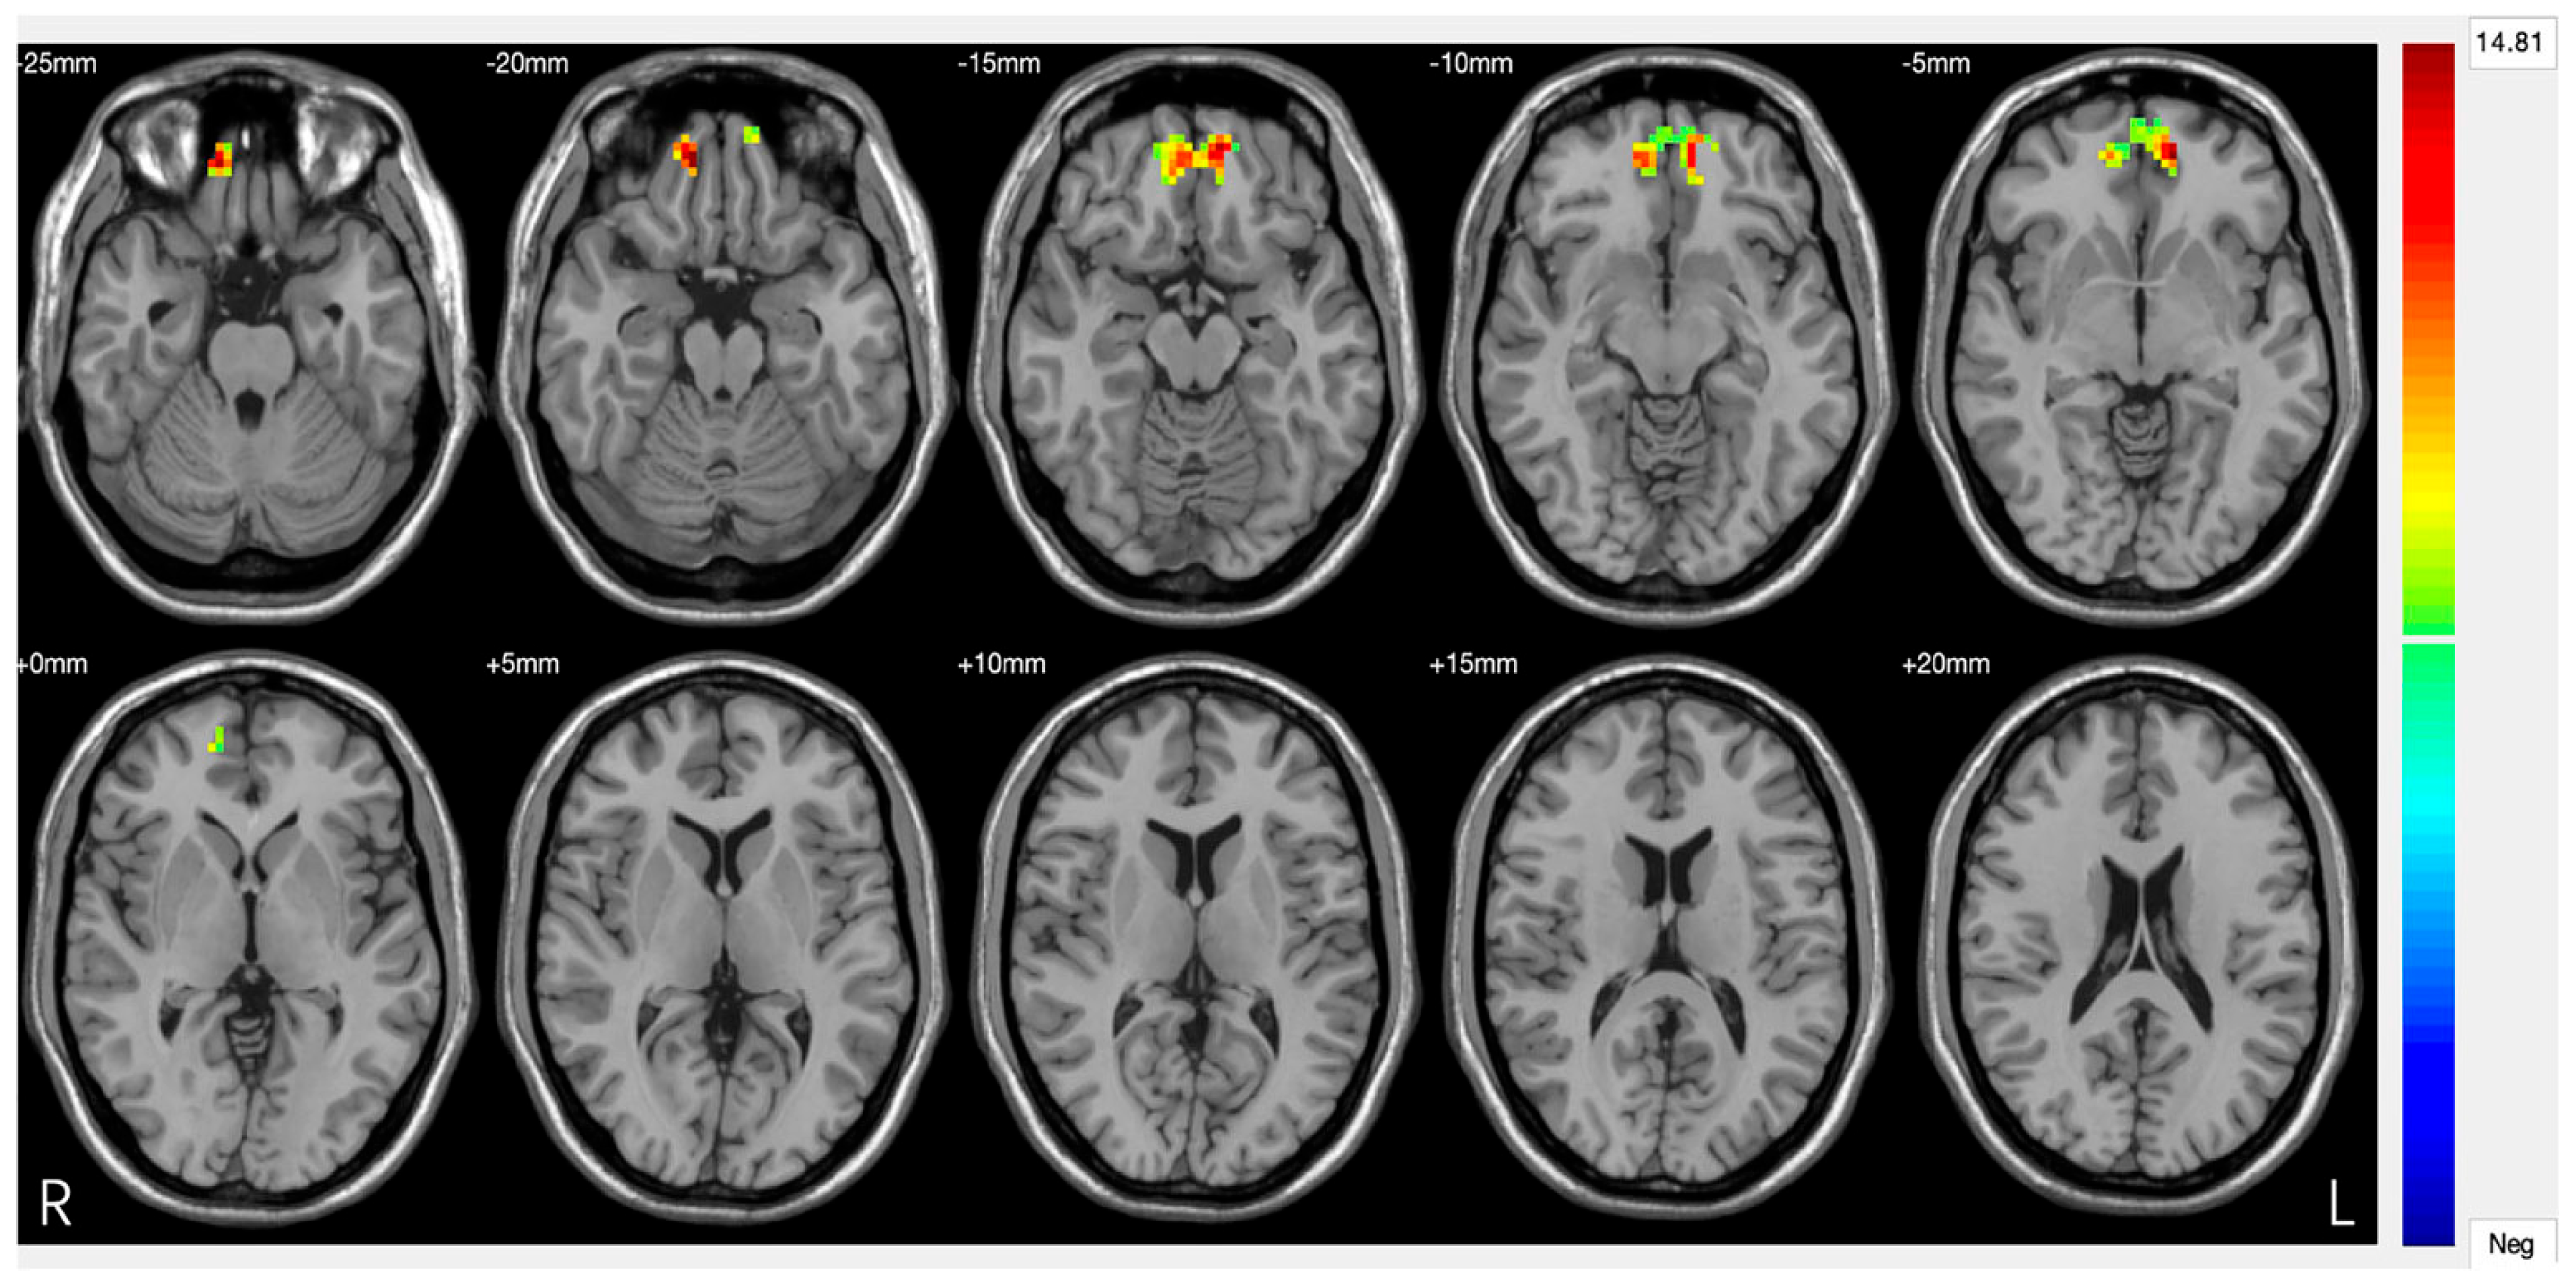

Figure 3.

Significant differences in amygdala–prefrontal cortex (PFC) functional connectivity (FC) among the major depressive disorder (DS) with a history of suicide attempts (SA), DS without a history of SA, and HC groups. Significant at p < 0.001, corrected by Gaussian random field (GRF) correction [68].